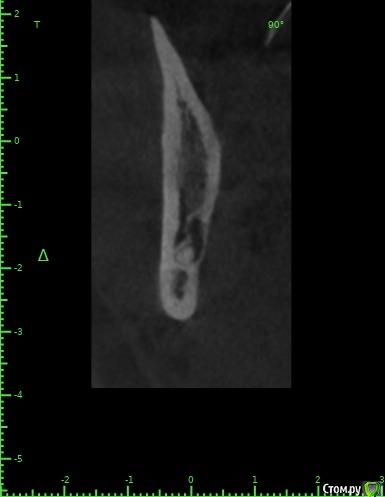

Женька Опубликовано 3 марта, 2021 Поделиться Опубликовано 3 марта, 2021 Коллеги, при коронэктомии есть какие-то нюансы? Или тупо отпиливаем коронку, сглаживаем острые края и зашиваемся? Или удалили бы полностью такого зверя? Ссылка на комментарий

kramer Опубликовано 3 марта, 2021 Поделиться Опубликовано 3 марта, 2021 Полностью конечно 1 Ссылка на комментарий

Женька Опубликовано 3 марта, 2021 Поделиться Опубликовано 3 марта, 2021 Полностью конечноПобаиваюсь что пучок травмирую пока доставать буду Ссылка на комментарий

kramer Опубликовано 3 марта, 2021 Поделиться Опубликовано 3 марта, 2021 Побаиваюсь что пучок травмирую пока доставать буду "Боишься - не делай, делаешь - не бойся" (с) Ссылка на комментарий

Raystom Опубликовано 3 марта, 2021 Поделиться Опубликовано 3 марта, 2021 Коллеги, при коронэктомии есть какие-то нюансы? Или тупо отпиливаем коронку, сглаживаем острые края и зашиваемся? Или удалили бы полностью такого зверя?Полностью, без вариантов. Ссылка на комментарий